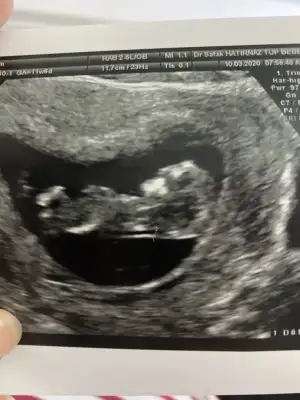

merhaba 12 haftalık hamileyim bende bugün ikili tarama yaptırdım cinsiyet tahmininizi alabilir miyim :)

Eklentiler

• E5C92BC7-7E7F-4A45-8611-64A3B20844EA.webp

E5C92BC7-7E7F-4A45-8611-64A3B20844EA.webp

40,6 KB · Görüntüleme: 51

• A6DDA7B7-A56E-42F6-8D66-E4AAC8182DA4.webp

A6DDA7B7-A56E-42F6-8D66-E4AAC8182DA4.webp

26,7 KB · Görüntüleme: 46